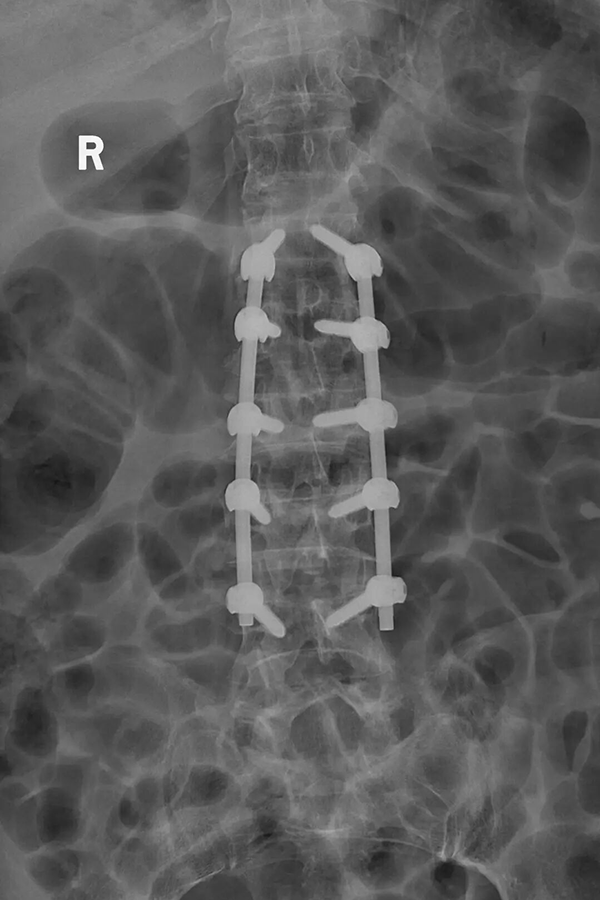

手术过程中,脊柱外科医疗团队凭借丰富的临床经验和精准的操作技巧,通过微创切口,沿肌肉自然间隙精准分离,避开重要神经和血管,顺利暴露入钉点。在C臂机的引导下,医生精准定位、逐一枚入十枚螺钉,术中创伤小,出血量极少。

从术前对老人身体机能的全面评估、量身定制个性化手术方案,到术中多学科团队精准协作、精细操作,再到术后一周即可顺利下地活动,这场 “十钉亦微创” 的手术,不仅成功治愈了患者的多节段脊柱爆裂性骨折,更以精准微创的技术为高龄患者筑牢生命安全防线。手术打破了 “高龄多节段骨折难治愈、术后恢复慢” 的传统认知,这不仅是脊柱微创技术实力的有力彰显,更是医者仁心的生动实践。

➜无需承受多枚螺钉穿刺带来的叠加创伤,哪怕像张大爷一样植入十枚螺钉,整体创伤程度也远远低于传统经皮微创手术。

➜该入路可以更清晰地呈现骨折区域与解剖构造,帮助医生精准植入螺钉、顺利完成穿棒固定,完美攻克了多节段骨折传统微创术式穿棒难度大、复位效果差的痛点,在保障手术效果的同时,最大程度降低手术创伤。